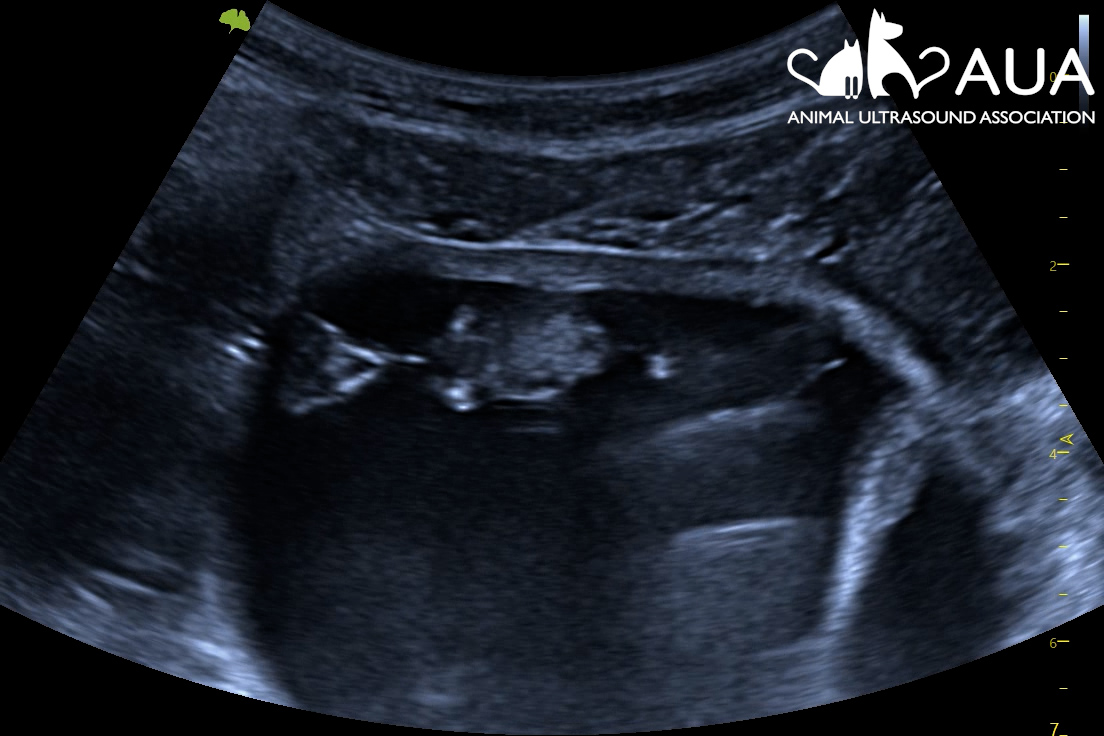

We confirmed 8 pregnancies today in Maidstone, Kent. Most of them were between 50 – 70 days, and it is surprising how tiny the foetus still is even at that stage of gestation. A human foetus at the same gestational age is about 8x larger; a feline fetus, 14x larger! Hence, when scanning you find yourself searching for a pea-sized foetus in a relatively large animal with a large, fluid-filled uterus. This involves moving your transducer along the uterine horns, and fanning back and forth, to try to spot a hiding future cria. At times, this is easier said than done, as alpacas are not always the most still and cooperative when having their abdomens touched.

We initially tried scanning them by moving the scanner to wherever they were being held, but we discovered this was a risky strategy as we dodged kicks and continually wiped alpaca spit and kicked dust off the machine. In the end, we managed to use the metal fencing to create a triangular pen for each alpaca to stand in, with me scanning through the bars. As well as containing them, this also seemed to calm them and make the experience less stressful for them.